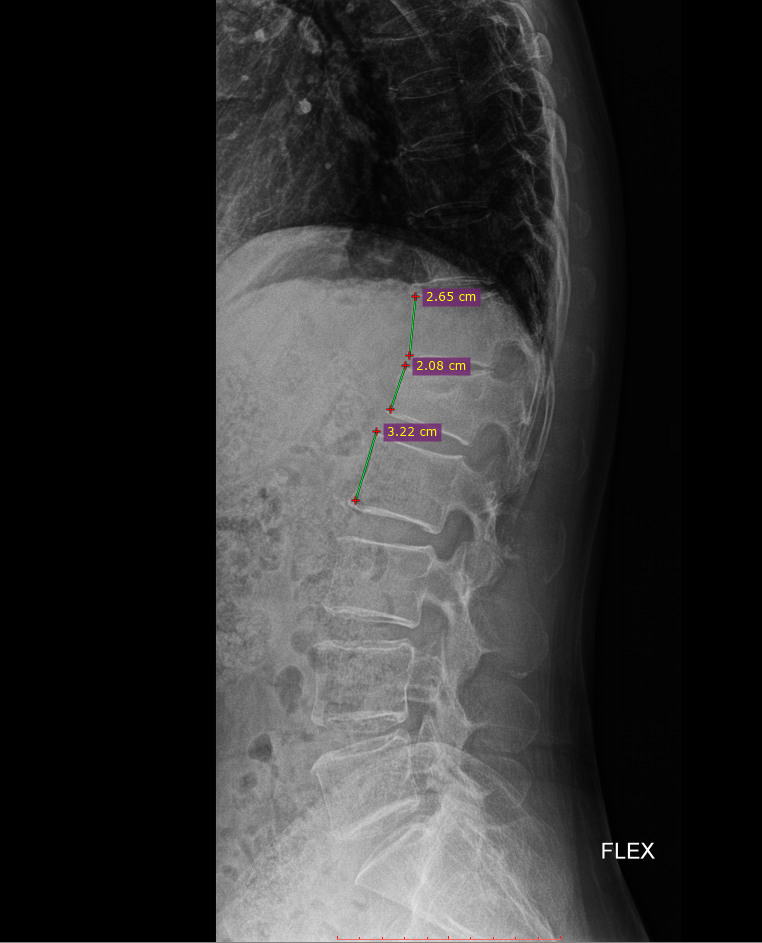

이 사건의 의뢰인은 상대방이 동석한 교통사고 피해자로서 사고 후 요통으로 ○○병원 응급실에 내원하였고 “제2요추폐쇄증후군” 진단을 받았다. 방사선 검사에서 “압박 골절”이 나타났습니다. 부상 초기에 척추의 추가 기형이 진행되거나 신경학적 증상이 나타나면 수술을 준비하고 며칠 동안 경과를 지켜보십시오. 다행스럽게도 통증은 신경학적 증상 없이 차차 가라앉았고, 정형외과를 통한 보존적 치료만이 상당 기간 지속되다가 치료가 종료되었다.

응급실 기록